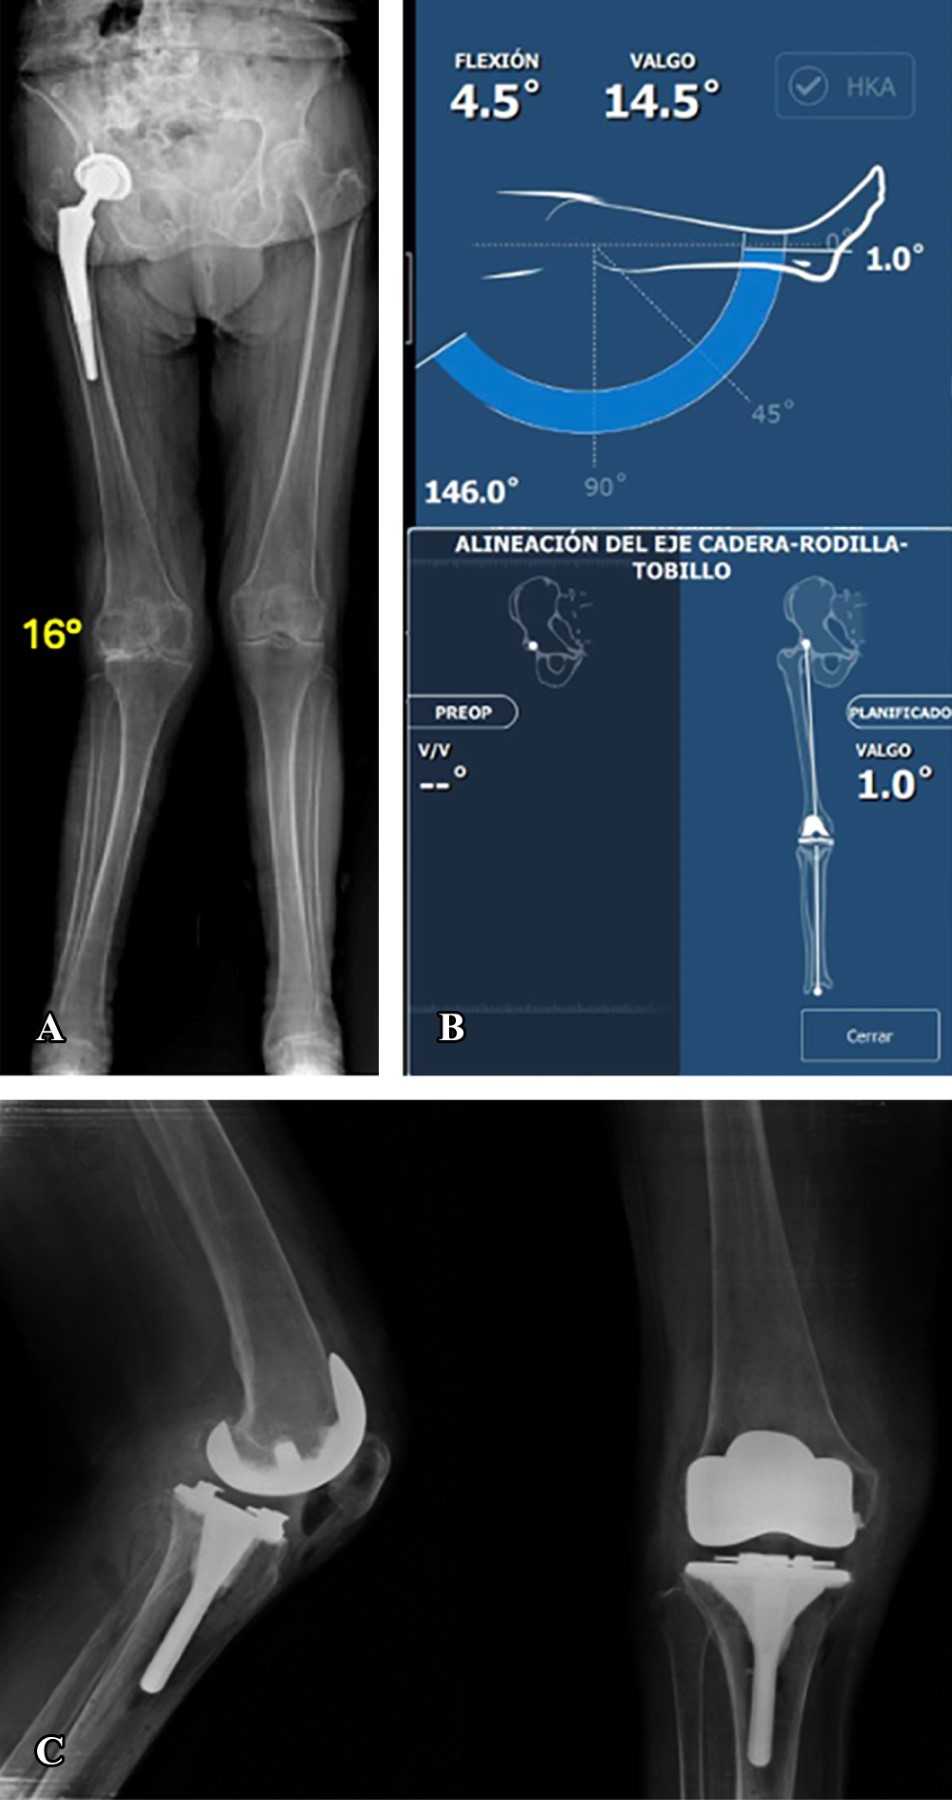

Nueve casos presentaron deformidad en varo (Figura 1) con un promedio de 8.89°. La alineación final resultante en cinco casos fue de 2.3° de varo en promedio, dos casos finalizaron con alineación neutra y dos con valgo de 1°.

Figura 1